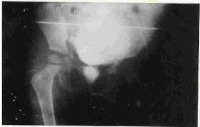

Dermatofibroma Of The Foot Mimicking Neurofibroma Radiologically

Dr. Agunloye A. M., O. M. Atalabi, A. O. Ogunseyinde, M. O. Obajimi, A. O. Adeyinka (Author)

14-15